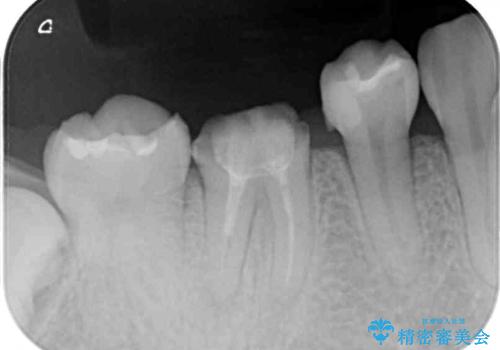

- セラミッククラウンが破損したため、職場近くのクリニックで治療開始したものの、当院への転院を希望して来院された患者様です。

クラウン再製作の際、提案された根管治療を開始したものの、処置の度に痛みを感じるとのことでした。

当院にて根管治療を行った後に、フルジルコニアクラウンにて補綴することとしました。

前医での根管治療の度に感じていた痛みの原因は分かりませんでしたが、元々違和感すらなかった歯であったので、速やかに根管治療を行った後に、ジルコニアクラウンを装着しました。

咬み合わせが強く、歯の高さが非常に低かったため、審美性には劣るものの、高強度であるフルジルコニアクラウンを採用しました。